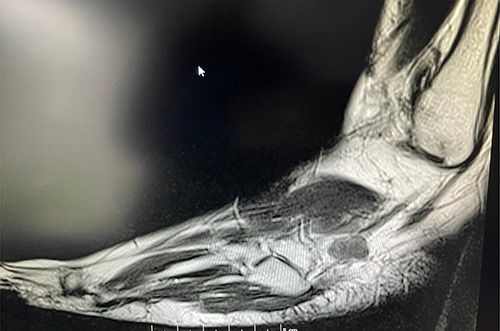

A 50-year-old lady presented to us with a lump in her left foot on the lateral aspect at the level of the calcaneocuboid joint for a 1-year duration, which was associated with pain. She consulted her GP who advised an US scan. This revealed a lump over the dorsum of the left foot on the lateral side. She also had a magnetic resonance imaging (MRI) scan which was indeterminate (Figs 3 and 4). It was reported as a suspected sarcoma. She was then referred to the Sheffield sarcoma unit where she underwent a biopsy of the swelling; which was reported as angiomyolipoma (a benign swelling). She was not keen on excision initially, but as the swelling increased in size and started becoming painful, she underwent an excision of the lesion under our care and the histopathologic examination of the excised sample confirmed it to be angioleiomyoma. The post-operative period was uneventful and she was discharged from our care after 10 weeks. At this time, she was symptom-free and had a pain score of 0/10.

T1 MRI image of the soft tissue lesion over the lateral foot in Patient 2, which shows a lesion isointense to hypointense to the muscle.

Similarly, in Case 2, the patient had an MRI scan which reported an indeterminate swelling suggestive of a possible sarcoma. As the MRI findings were not characteristic of the MRI findings of an angioleiomyoma, such as T1: isointense or hyperintense to muscle, T2: heterogeneous and slightly hyperintense to muscle and T1 C+ (Gd): homogenous to heterogeneous enhancement, suspicion of the sarcoma was reported from the MRI scan findings and referral to sarcoma unit was advised. This clearly shows that the US and the MRI scan findings can suggest a different diagnosis, and a confirmed diagnosis was only established following excision and histopathological examination of the excised lesion. Usually, angioleiomyomas have a peripheral low-intensity signal rim corresponding to a fibrous pseudo capsule with adjacent vascular structures with isointense or hypointense to muscle on T1 images and heterogeneous and slightly hyperintense to muscle on T2 images.